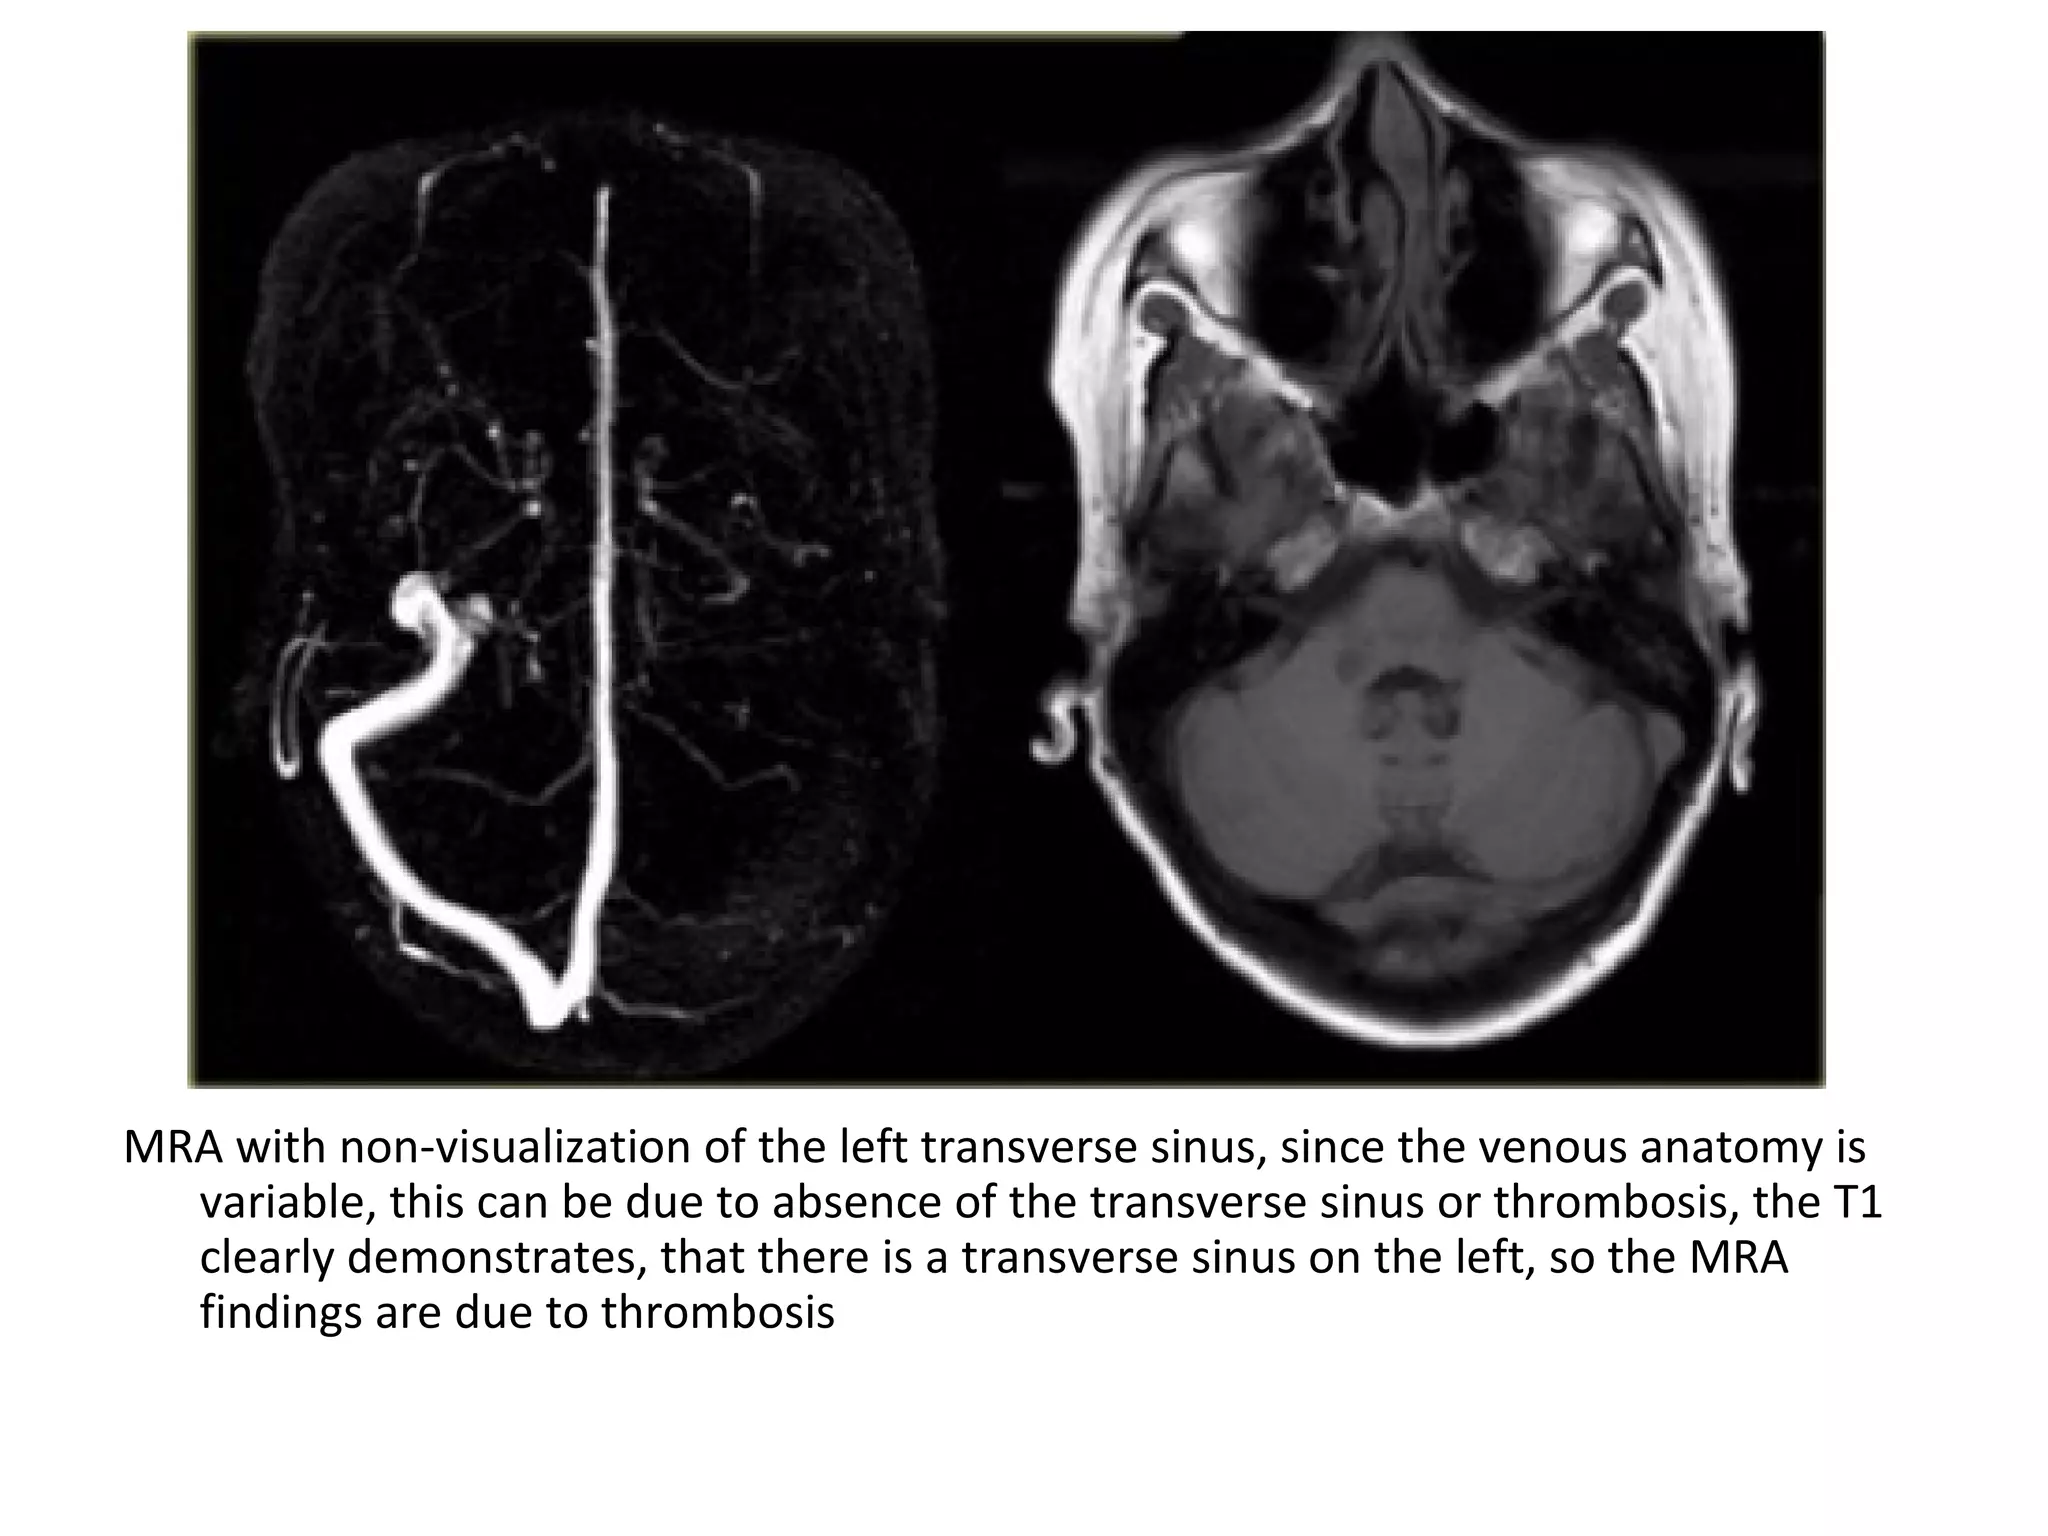

MRA with non-visualization of the left transverse sinus, since the venous anatomy is

variable, this can be due to absence of the transverse sinus or thrombosis, the T1

clearly demonstrates, that there is a transverse sinus on the left, so the MRA

findings are due to thrombosis